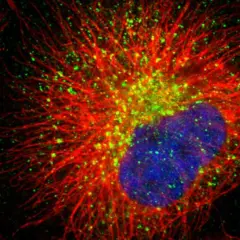

468. Sartorius - Cell Instance Segmentation

Detect single neuronal cells in microscopy images |

Prize: $75,000 Team: 1,505 Kind: Featured Metric: IntersectionOverUnionObjectSegmentation Year: 2021 |